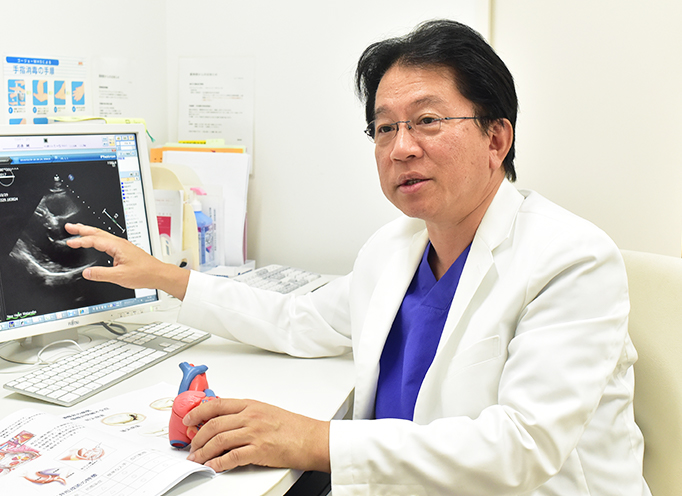

循環器内科部長

黒岩 信行 Nobuyuki Kuroiwa

Profile

ニューハート・ワタナベ国際病院

循環器内科部長

黒岩 信行 Nobuyuki Kuroiwa

【経歴】

【資格】